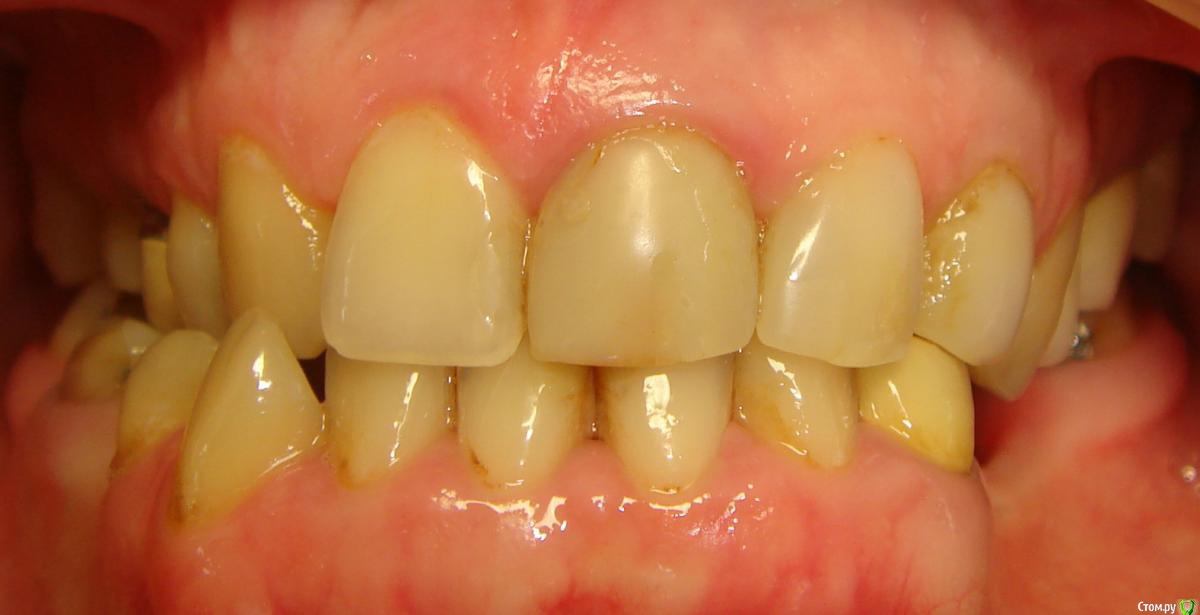

Здравствуйте, Коллеги! Хочу спросить совета по такому случаю. Пациентка 33 года. В детстве удалили 12 зуб, пространство закрыли на съемном аппарате. В подростковом возрасте удалили все остальные отсутствующие зубы. Сейчас носит бюгель. Вопрос такой: заниматься ли мне, как ортодонту формированием полноценного межчелюстного соотношения, или просто решить локальные проблемы и отдать на функциональную реабилитацию ортопеду? И если все-таки заниматься мне, то как??? Лечение такого третьего класса - элементарно для многопетлевой при наличии адекватной опоры, но вот такая адентия заставляет меня сомневаться. Заранее спасибо за ответы!